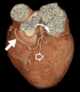

Coronary artery disease - hyperlipidemia - hypertension - diabetes - osteoporosis

Statins, also known as HMG-CoA reductase inhibitors, are a class of lipid-lowering medications that reduce illness and mortality in those who are at high risk of cardiovascular disease. They are the most common cholesterol-lowering drugs.Low-density lipoprotein (LDL) carriers of cholesterol play a key role in the development of atherosclerosis and coronary heart disease via the mechanisms described by the lipid hypothesis. [Source: Wikipedia ]